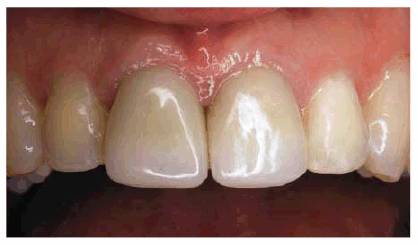

Figure 23-14G and H: Note the improvement in the smile by comparing the before and after pictures.

Figure 23-14I and J: These before and after pictures show how much better proportioned the larger teeth appear in full face. (Reproduced with permission from Goldstein RE. Change your smile. 3rd edn. Carol Stream, IL: Quintessence, 1997:122.)

laminates were used to create a symmetric arch with proper spacing (see Figure 23-14F). The improvement by the final result can be

seen by comparing the before and after smiles (see Figures 23-14G and H). Note how the increased tooth size is

RESULT: Frequently, orthodontics is required to reposition teeth

together to avoid the overly contoured appearance of restored teeth. Although

this treatment could have been employed, the patient chose immediate esthetic